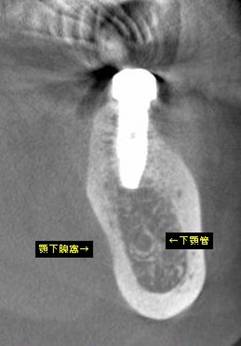

術後のCBCT

インプラントの重大な事故は下顎管から十分な距離をとれば防げます

抜歯部位にインプラントを追加しました。CBCT